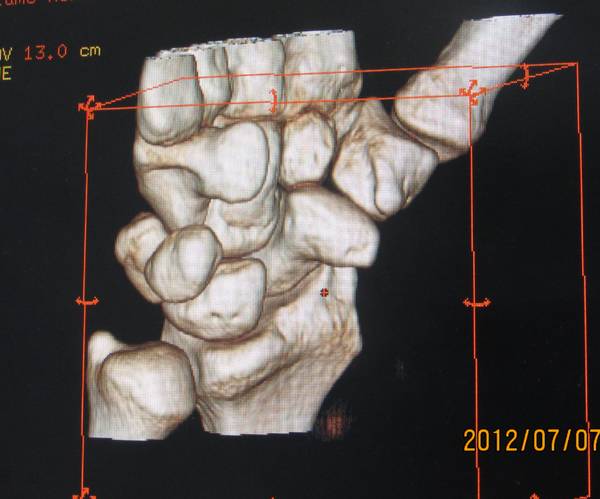

今天去ct室拍了一组舟骨骨图片

在机房看的动态的图像,想怎么看就怎么看

随便转

对骨质结构情况一目了然

太清楚了

4.png

2.png

1.png

3.png